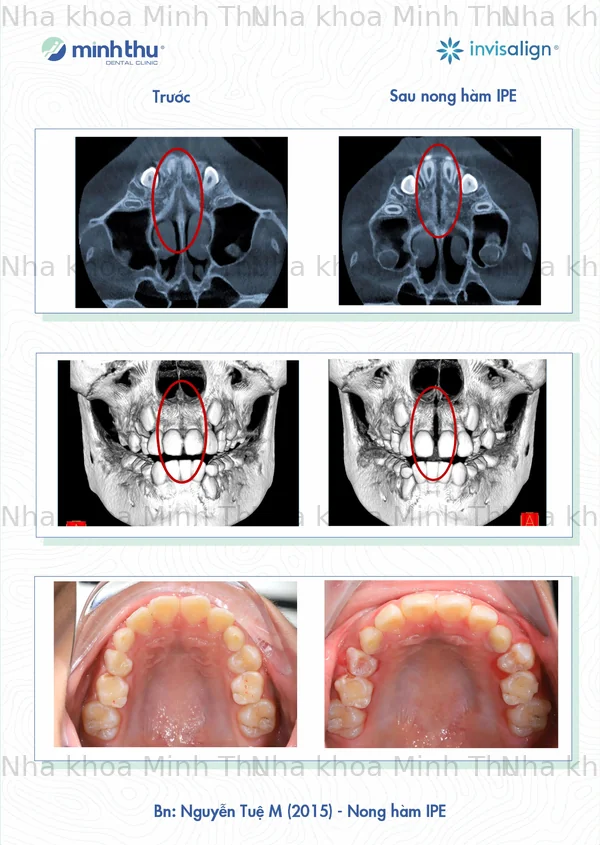

Một số ca nong hàm IPE tại Nha Khoa Minh Thu, kết quả phụ thuộc vào tình trạng và mức độ đáp ứng điều trị của mỗi bệnh nhân.